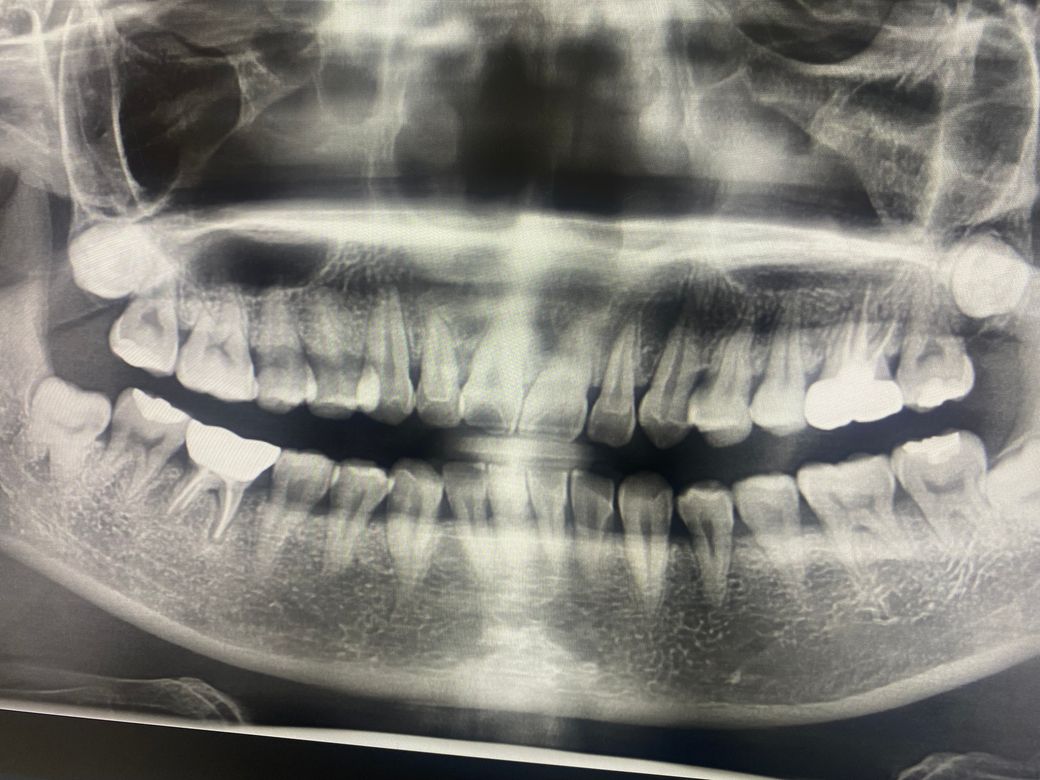

크라운 한 부분이 치주염이랬고

첫번째 사진 같이 크라운 한 치아에 흰고름이 나오는 증상으로 어제 잇몸치료를 했습니다(염증 긁어내는 치료)

• 1번 째 사진